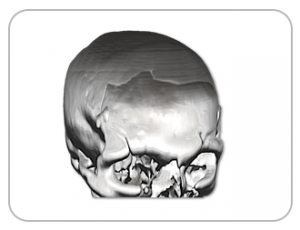

DEFECT FROM HEAD INJURY

IMPLANT FABRICATED USING 3D PRINTING TECHNOLOGY

POST-SURGERY SCAN IMAGE AFTER 24 MONTHS SHOWING PERFECT IMPLANT FIT